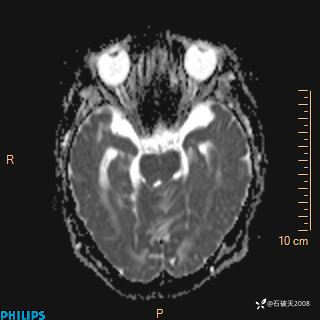

T2

FLAIR